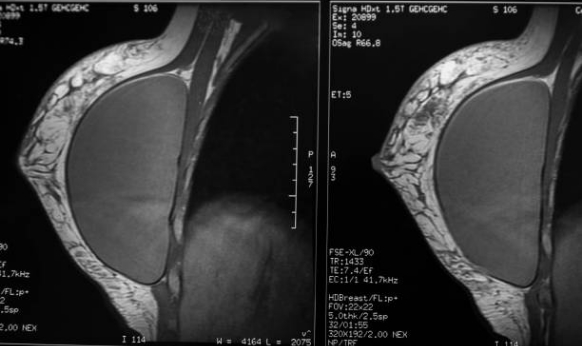

Uzun yıllardır gerçek nedeni bulunamayan bu kanser türü ile ilgili oldukça ciddi bir bilimsel araştırma yapıldı. Sonuçlar Amerika'daki New Haven Üniversitesi'nin 15 Eylül tarihli basın bülteninden dünyaya duyuruldu. Hücresel ve Moleküler Biyoloji Bölüm Başkanı ve Üniversite'nin Lyme Araştırma Grubu Direktörü, dünyaca ünlü Biyoloji Profesörü Dr. Eva Sapi ve ekibinin Lyme hastalığına neden olan spiroket bakteri Borrelia burgdorferi ve meme kanseri arasındaki bağlantıyı ortaya çıkardı. Bu araştırma çerçevesinde 400'den fazla invazif meme kanseri dokusu içerisinde önemli sayıda örnekte Borrelia bakterisi pozitif tespit edildi.

Meme kanseri ile Borrelia bakterisi arasında ki bağlantı ile ilgili konuşan Prof. Dr. Çetin; “Kanser her şeyden önce bir DNA hastalığıdır. Borrelia spiroket bakterisi enzimleri baskıladığından, DNA'nın tamir mekanizmasını da bozar. Bu da kansere yol açar. Kanserin temelinde yatan diğer bir önemli neden de oksijen eksikliğidir. Borrelia kanın kalınlaşmasını sağlamak suretiyle oksijenin dokulara taşınmasını güçleştirir. Düşük pH Borrelia için en uygun ortamdır. İnsan vücudunda en çok epitel hücreleri kanser hücresine dönüşüyor. Meme, kalın bağırsak ve prostat epiteli gibi” dedi.